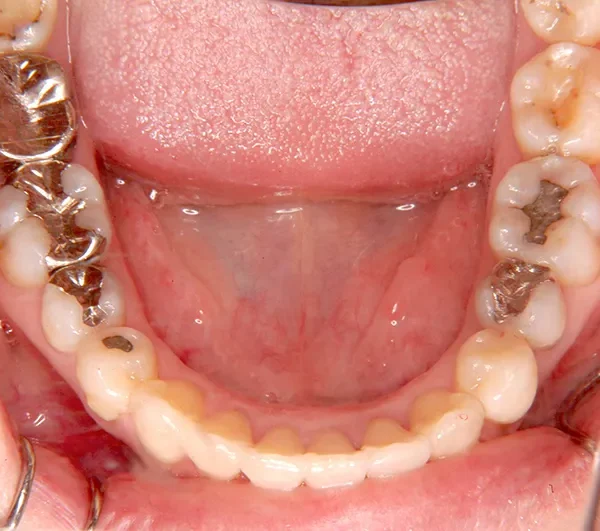

初診時年齢 40歳以上 (女性) 主訴 上下のがたがた・噛み合わない

診断名 叢生 装置名

特徴 ゆがんで生えている

状態 ガタガタ・でこぼこに生えている(叢生)

八重歯(叢生)

上下のがたがたと噛み合わない事を主訴に来院されました。

歯は抜かずに矯正治療しました。

治療回数35回、2年8ヶ月の治療期間で矯正治療を終了しました。